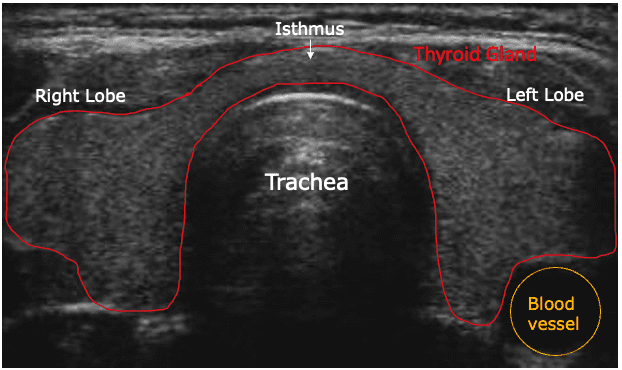

Ultrasound of Thyroid Gland

Thyroid ultrasound is a sound wave picture of the thyroid gland taken by a hand-held instrument and translated to a 2-dimensional picture on a monitor. It is used in diagnosis of tumors, cysts or goiters of the thyroid, and is a painless, no-risk procedure.

A thyroid ultrasound is a painless, non-invasive imaging test that uses sound waves to create a picture of the thyroid gland. It's the most common way to image the thyroid and is used to diagnose conditions like cysts, tumors, and goiters.